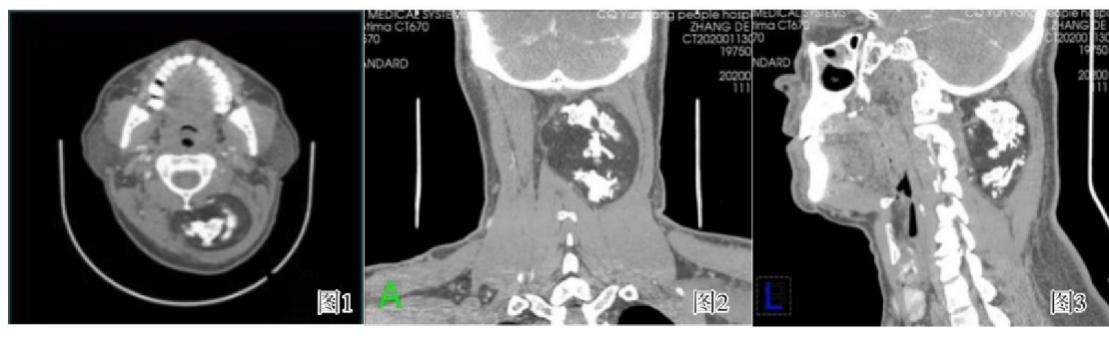

成人颈项部间叶性错构瘤CT增强图像

来源丨向武昌,杨小蓉. 成人颈项部间叶性错构瘤一例[J]现代医用影像学. 2021,30(04).